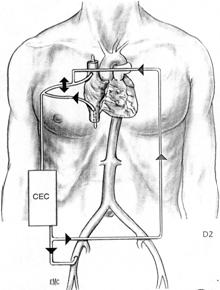

1) Arresto di circolo in ipotermia profonda

Il paziente viene posto in circolazione extracorporea ( CEC ) dopo avere incannulato l'arteria femorale e l'atrio destro, mediante due cannule o una singola ( two stage ) cannula e la sua temperatura corporea abbassata progressivamente a 15-18 °C. A questa temperatura la CEC viene fermata ed il sangue del paziente raccolto dentro l'ossigenatore ed il cardiotomo, in modo da rendere il campo chirurgico esangue. La protezione cerebrale viene migliorata apponendo alcuni sacchetti di ghiaccio attorno alla testa del paziente, che è stato preventivamente posizionato in Trendelemburg. L'ipotermia profonda, riducendo l'attività metabolica cellulare, consente l'arresto di circolo per un intervallo di tempo cosiddetto "sicuro", in cui le cellule, utilizzando le riserve d'energia disponibili, non vanno incontro ad alterazioni irreversibili e riprendono la loro normale funzione dopo il ripristino della normotermia.

Il periodo sicuro è influenzato da diversi fattori quali: la velocità di raffreddamento, la temperatura cerebrale media, la pressione arteriosa, il livello di catecolamine, il grado di ipotermia. Studi recenti indicano che se l'ipotermia è dell'ordine di 15-18°C il periodo "sicuro" ha la durata di circa 45 minuti e che i livelli di ATP si riducono del 65%. E' stato dimostrato che tra i 45 e i 60 minuti, il rischio di danni cerebrali irreversibili è del 65% e che oltre i 60 minuti il danno cerebrale interessa il 100% dei casi.

2) Ipotermia profonda, CEC e perfusione cerebrale retrograda

Questa tecnica prevede l'inversione del flusso ematico sulla linea venosa durante la fase di arresto di circolo. La CEC viene iniziata dopo avere incannulato le due vene cave e l'arteria femorale. Si raffredda progressivamente il paziente e non appena si raggiunge la temperatura di 15-18 °C si ferma la CEC e si inizia la perfusione retrograda della vena cava superiore collegata alla linea arteriosa, a bassi flussi, 500 - 800 ml/min/mq s.c., mantenendo una pressione cavale superiore compresa tra 20 e 25 mmHg. Il sangue refluo dal circolo cerebrale viene aspirato a livello dell'aorta ascendente.

Tale tecnica consente di prolungare oltre il limite dei 60 minuti il tempo di arresto di circolo.

3) Ipotermia profonda, CEC e perfusione anterograda

La caratteristica di questa tecnica è che durante la fase di arresto di circolo, viene eseguita la perfusione cerebrale anterograda continua, mediante la cannulazione selettiva ed il collegamento alla linea arteriosa della CEC, del tronco arterioso anonimo e della carotide comune sinistra.